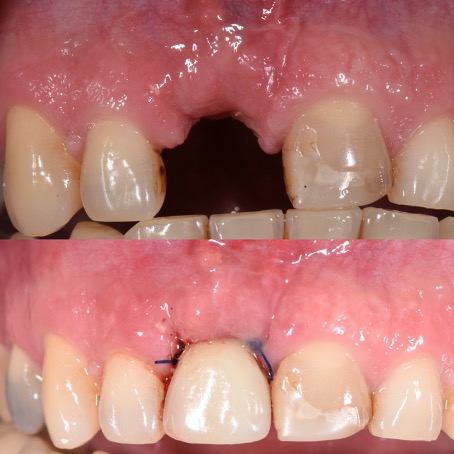

Cas esthétique d'implant unitaire

Mise en charge immédiate

Avec un implant unitaire et la mise en charge immédiate dans les zones esthétiques (quand c’est possible et selon le cas observé), la phase de cicatrisation, normalement de quelques semaines, se déroule avec une dent provisoire fixe (couronne provisoire vissée) qui permet d’éviter l’installation d’une prothèse provisoire amovible (dentier). Cela épargne aux patients de subir une intervention supplémentaire et il s’agit aujourd’hui d’une procédure standardisée, très confortable et très appréciée par les patients. C’est uniquement dans les cas exceptionnels, comme par exemple en cas d’infections aiguës, qu’il est préférable d’extraire d’abord la dent délabrée et de poser l’implant seulement lorsque l’inflammation est résolue.